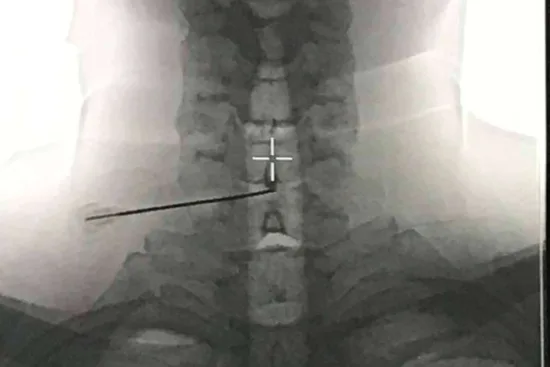

En este procedimiento, se aplica ozono en el interior del disco enfermo mediante una aguja guiada por rayos X. El objetivo es reducir el tamaño de la hernia o protrusión, aliviar la compresión radicular, proporcionar un potente efecto antiinflamatorio, permitir la regeneració de los tejidos y ofrecer una analgesia duradera en las áreas circundantes.